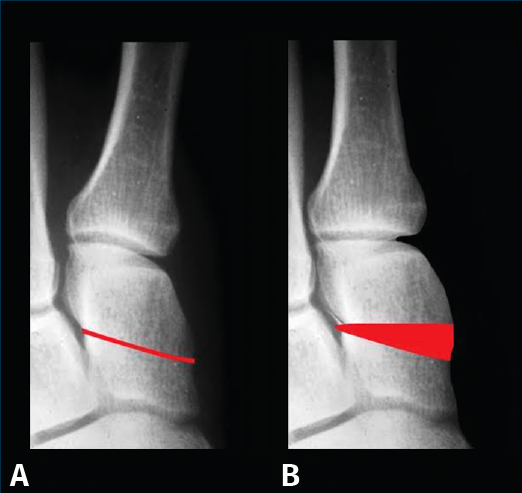

Proponemos una clasificación práctica derivada de las propuestas por D. J. Hatch et al.(32) y de J. S. Kim y K. W. Young(33) para determinar la situación de los sesamoideos en la proyección axial, que exponemos a continuación, utilizada en este trabajo y que puede ser de ayuda para realizar el tratamiento quirúrgico más adecuado. En ella se valora “la relación espacial” del rodete con la cara articular plantar del primer metatarsiano:

- Grado 0: normal. No pronación. No desplazamiento medial del primer metatarsiano. Sesamoideos estables (Figura 5A).

- Grado I: no pronación. Desplazamiento medial del primer metatarsiano. Sesamoideos subluxados. Osteotomía del primer metatarsiano + cerclaje fibroso (Figura 5B).

- Grado II: pronación. Desplazamiento medial del primer metatarsiano. Los sesamoideos están en su lugar, pero en las radiografías parecen luxados. Osteotomía desrotatoria triplanar del primer metatarsiano vs. artrodesis cuneometatarsiana triplanar (Figura 5C).

- Grado III: pronación + desplazamiento medial del primer metatarsiano. Sesamoideos subluxados. Osteotomía desrotatoria triplanar de primer metatarsiano vs. artrodesis cuneometatarsiana triplanar + cerclaje fibroso (Figura 5D).

Figura 5. Clasificación de la posición de los sesamoideos en proyección coronal.